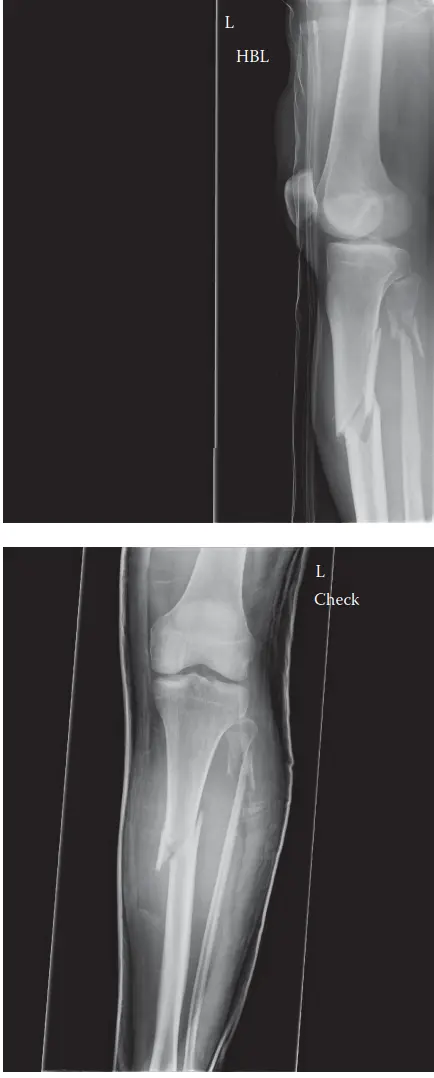

التصوير بالأشعة السينية

تُعد الأشعة السينية (X-rays) هي الخطوة التشخيصية الأولى والأكثر شيوعًا. يتم الحصول على صور بالأشعة السينية للساق المصابة من زوايا مختلفة (أمامية خلفية وجانبية)، ويجب أن تشمل الصورة كامل عظمة الساق، من مفصل الركبة إلى مفصل الكاحل، لتقييم الكسر بالكامل والبحث عن أي إصابات مرافقة.

ما تُظهره الأشعة السينية:

*

موقع الكسر:

تحديد ما إذا كان الكسر في الثلث القريب من جسم عظمة الساق.

نمط الكسر:

هل هو كسر مائل، عرضي، حلزوني، أو مفتت (متعدد الشظايا)؟

الإزاحة والزاوية:

مدى تحرك أجزاء العظم المكسورة عن مكانها الطبيعي، ووجود أي انحناء أو زاوية غير طبيعية.

تقصير العظم:

مدى وجود تقصير في طول الساق.

كسر الشظية المصاحب:

غالبًا ما يظهر كسر في عظمة الشظية في نفس مستوى كسر القصبة.

استبعاد الامتداد داخل المفصل:

تُظهر الأشعة السينية ما إذا كان الكسر يمتد إلى مفصل الركبة أو الكاحل، على الرغم من أن التصوير المقطعي المحوسب يكون أكثر دقة في هذا الصدد.